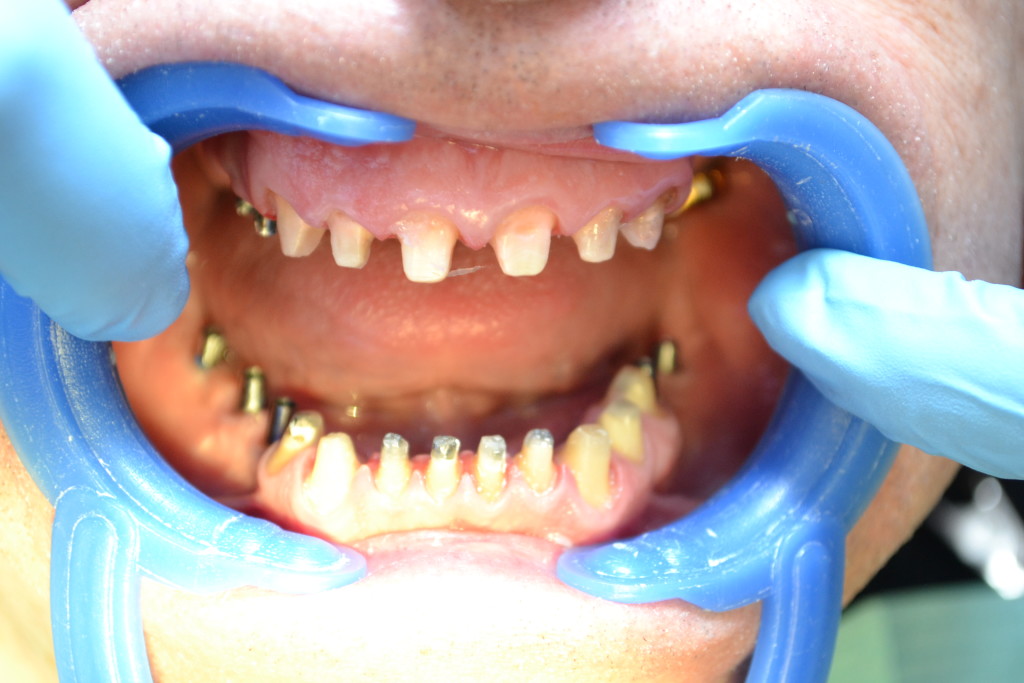

Тотальное протезирование двух челюстей, безметалловые коронки E-max, установленные на вживленные имплантаты Ankylos Dentsply Friadent.

- вживленные имплантаты

- подготовка: препарация + абатменты